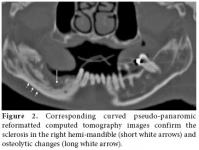

Together with the past history of long-term alendronate treatment and occurrence after tooth extraction, relevant clinical symptoms and conventional radiographic findings led to the suspicion of ONJ in this patient. We immediately ordered dental computed tomography (CT) which revealed sclerosis and osteolytic changes in the right mandible. This confirmed the diagnosis of osteonecrosis (Figures 2, 3). The patient also consulted with dental surgeons, and since there was no pathologic fracture, extra-oral fistulae, or osteolysis extending to the inferior border of the mandible, the disease was accepted to be in the second stage. Surgery was not recommended, and conservative management was started. The patient was advised to discontinue the alendronate treatment, and the etanercept treatment was also stopped. A good oral hygiene regimen using antibacterial tooth rinse was recommended. Her complaints and symptoms alleviated gradually. A control panoramic radiography taken after one year of bisphosphonate withdrawal displayed healing of the exposed bone (Figure 4).